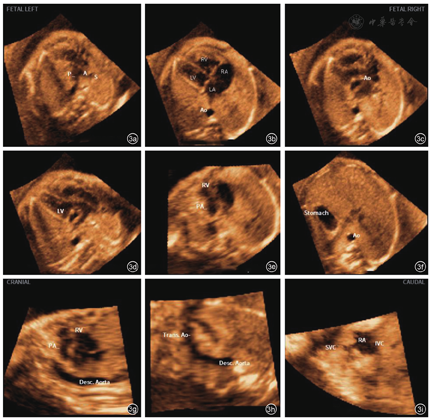

什么是超声容积探头妇产科超声影像学丨胎儿心脏超声智能导航技术显示胎儿完全型大动脉转位诊断切面的应用价值_https://www.jmylbn.com_新闻资讯_第6张

图3 应用5D Heart联合VIS-Assistance®技术显示1例24周cTGA胎儿的9个心脏超声诊断切面。图a为三血管气管切面(仅见一条大血管,上腔静脉位于右侧);图b为四腔心切面(无明显异常);图c为五腔心切面(无明显异常);图d为左心室流出道切面(平行走行的两条大血管,起源于右心室的血管未见分支/起源于左心室的血管可见分支进入胎儿肺组织);图e为右心室流出道切面(主肺动脉交叉环抱关系消失);图f为胃泡切面(无明显异常);图g为动脉导管弓切面(无法正常显示);图h为主动脉弓切面(无法正常显示);图i为上下腔静脉及右心房切面(无明显异常)

在本研究中,2名经验相对不足的超声医师经过培训后,应用5D Heart智能导航技术,对在任意胎方位下的以4CV为基础获得的15例不同孕周的cTGA胎儿心脏超声容积数据进行了在机后处理和图像分析。研究结果显示,86.7%的容积数据成功显示3VT切面,在该切面中,有86.7%的图像成功显示出仅见1条大血管,同时93.3%的图象能够显示出上腔静脉,而不是正常情况下的3个血管,此切面显示出的血管数目异常,高度提示胎儿心脏存在异常,而这种数目的异常也可以见于其他的动脉圆锥干畸形。15个容积数据中,LVOT显示率为80.0%,其中73.3%的容积数据显示出两条大血管平行走行,同时显示起源于解剖右心室的大血管未见分支而起源于解剖左心室的大血管走行较短距离后即可见分支,在这一切面上的所见,提示检查者起源自右心室的大血管是主动脉,而肺动脉则起源于左心室,两条大血管的位置关系是平行走行而不是正常情况下的交叉环抱关系,以上这些异常改变是胎儿cTGA最具特征性的超声表现。同时86.7%的容积数据在RVOT显示原本主动脉和肺动脉的交叉环抱关系消失,进一步提示检查者两条大血管位置排列关系存在异常。